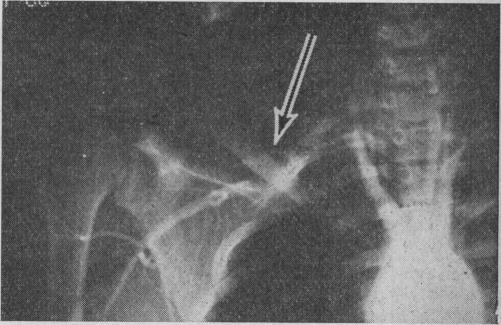

PULMONARY EMBOLISM.

Br Med J. 1963 Oct 5;2(5361):830-5. doi: 10.1136/bmj.2.5361.830.